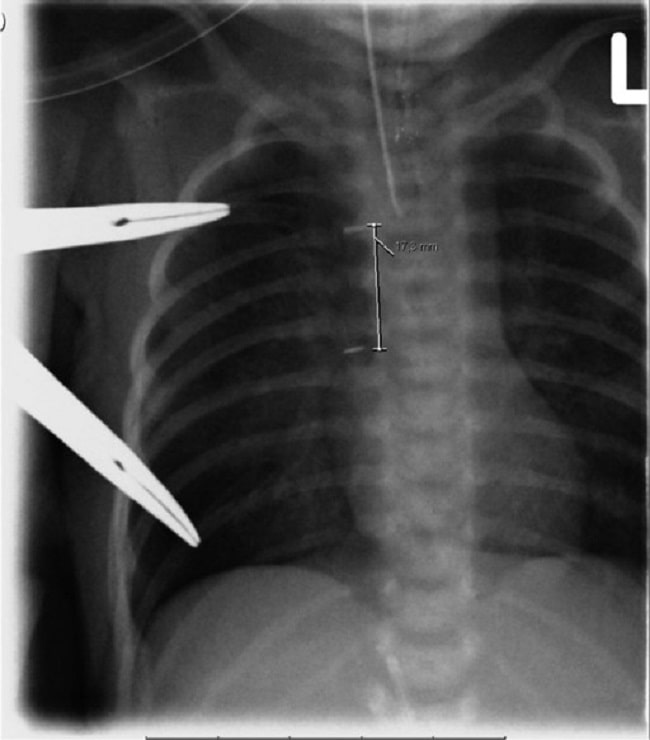

Rontgen thorax dengan menggunakan udara sebagai kontras dapat menjadi pemeriksaan penunjang untuk mengonfirmasi diagnosis atresia esofagus. Bila terdapat distal TEF pada pasien, udara abdomen akan tampak pada rontgen dan abdomen tampak distensi.[1,3]

Dengan menggunakan nasogastric tube atau orogastric tube yang bersifat radioopak dengan ukuran ukuran 8 French untuk bayi preterm dan ukuran 10 French untuk bayi aterm, dapat dilakukan pemeriksaan patensi esofagus dengan memasukkan selang melalui hidung atau mulut hingga ke gaster.[16]

Jarak normal menuju gaster pada bayi adalah 17 cm. Pada pasien dengan atresia, selang akan berhenti setelah masuk dengan jarak sekitar 10 hingga 12 cm.

Walau demikian, terdapat kemungkinan inakurasi hasil karena selang dapat menggulung di area sebelum atresia esofagus dan dipersepsikan sebagai selang berhasil masuk. Untuk itu, perlu dilakukan pemeriksaan rontgen thoraks posisi posteroanterior (PA) dan lateral untuk mengonfirmasi posisi selang setelah pemasangan.[16]

Gambar 3. Hasil Rontgen Atresia Esofagus dengan Traksi. Sumber: van der Zee DC, Gallo G, Tytgat SHA, Openi, 2015.

Gambaran rontgen juga sebaiknya memperlihatkan seluruh abdomen dengan baik. Karena pada pasien atresia esofagus, gambaran udara di perut menunjukkan bahwa terdapat distal fistula, dan adanya udara di usus dapat menyingkirkan kemungkinan atresia duodenal.[16]

Gambaran rontgen thoraks juga dapat memberikan informasi mengenai gambaran jantung beserta posisinya, letak arkus aorta dan ada tidaknya anomali vertebra dan tulang iga, serta memperlihatkan ada tidaknya infiltrat pada paru.[16]